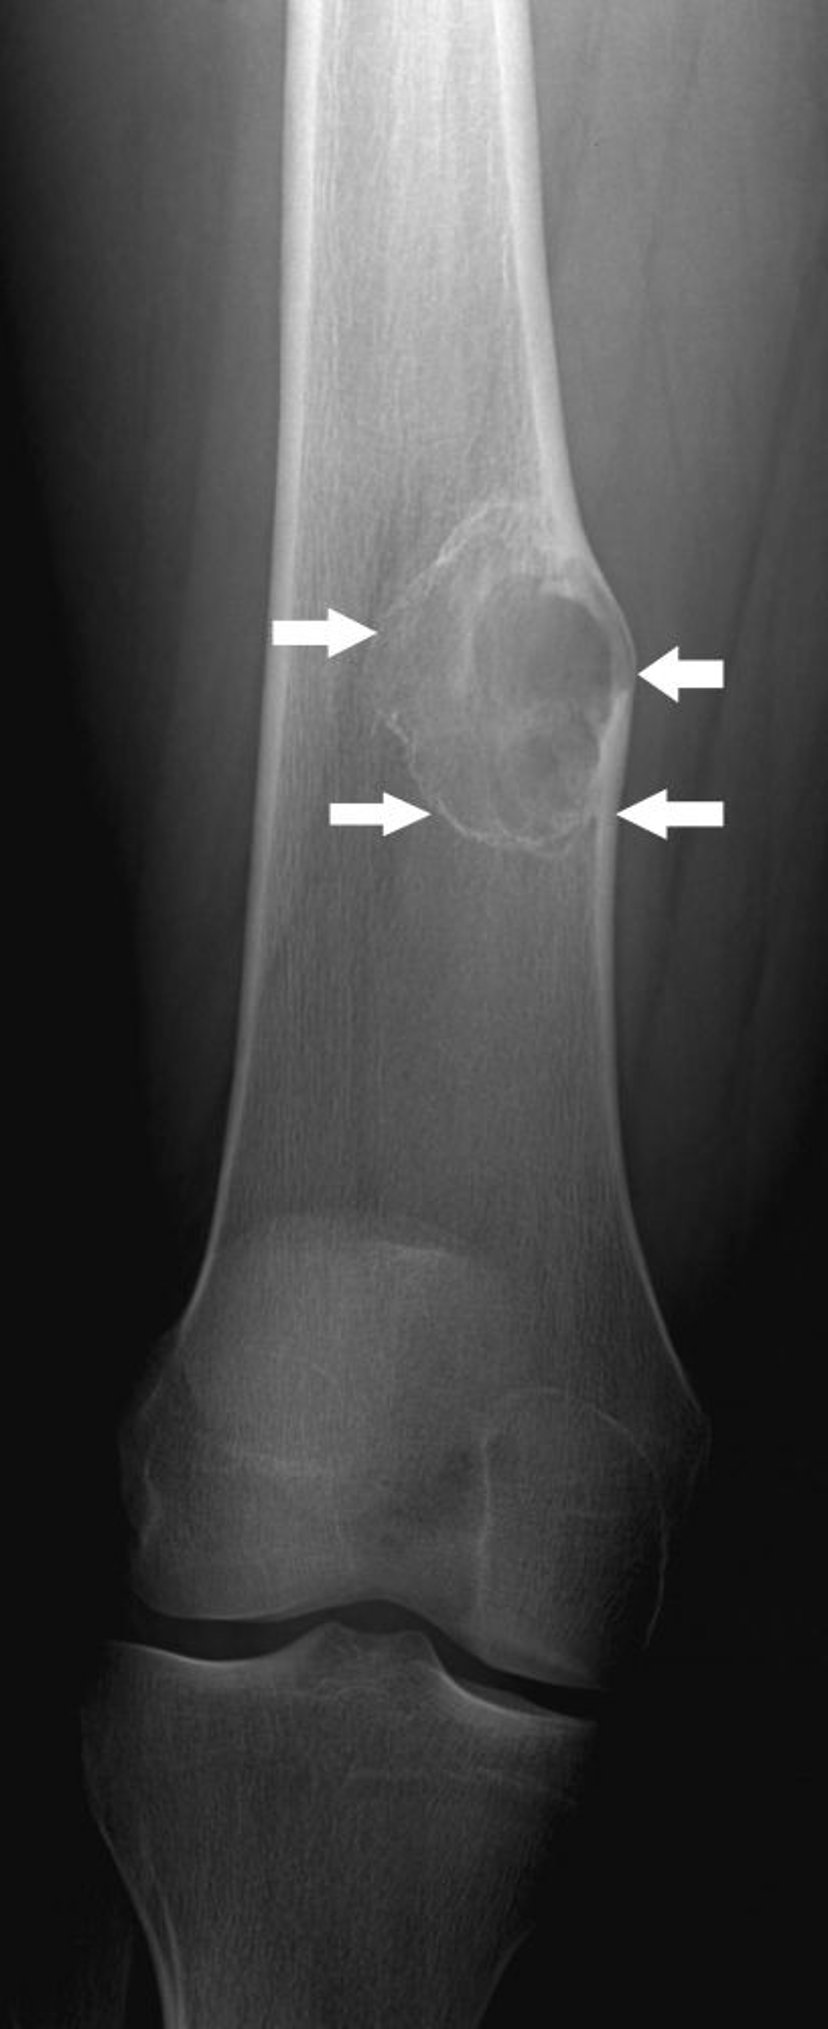

Radiografia del ginocchio che mostra un condromixofibroma (frecce) sull’osso dello stinco sotto al ginocchio.

Per gentile concessione di Michael J. Joyce, MD e Hakan Ilaslan, MD.

Il trattamento dei fibromi condromixoide consiste nella rimozione chirurgica, che in genere è curativa. A volte, però, questi tumori si ripresentano.